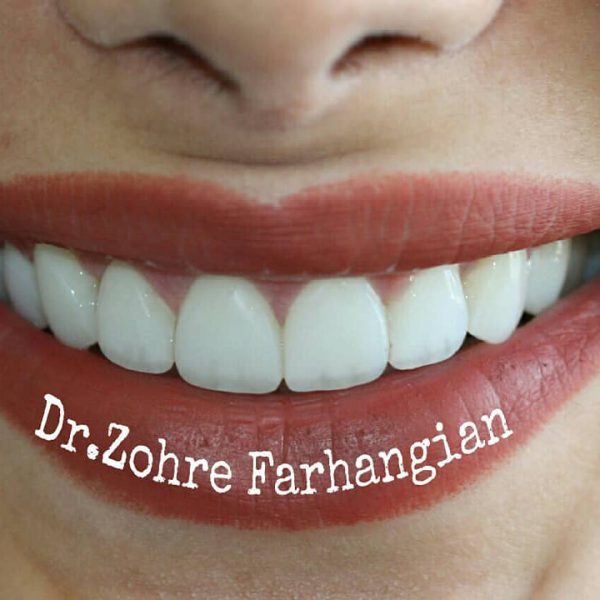

نمونه کار شماره ۱۹ کامپوزیت ونیر

کامپوزیت ونیر دندانهای فک بالا و پایین

مراحل درمان به شرح زیر:

۱.حذف ونیرکامپوزیتهای معیوب قبلی

۲.اصلاح ناقرینگی لثه دردندانهای قدامی(لیفت لثه)

۳.کامپوزیت ونیر دندانهای فک بالا و پایین

به کامپوزیتهای قبلی بیماردقت کنید که فاقد هرگونه آناتومی و ظرافت بوده و قوس لبخند کاملا به شکل یک خط صاف و غیر اصولی بوده، درست انتخاب کنید و یک مسیر را چند بار نروید😊

دکتر زهره فرهنگیان

متخصص دندانپزشکی ترمیمی و زیبایی در کرمانشاه